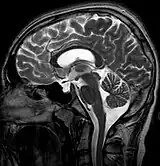

| MRI of Empty Sella | |

Empty sella syndrome is the condition when the pituitary gland shrinks or becomes flattened, filling the sella turcica with cerebrospinal fluid instead of the normal pituitary.[2] It can be discovered as part of the diagnostic workup of pituitary disorders, or as an incidental finding when imaging the brain.[1]